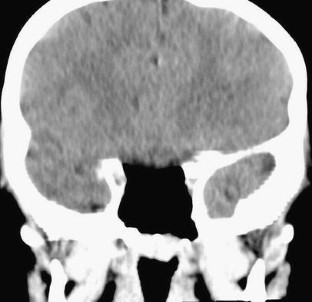

Mucocele of the sphenoid sinus

The sphenoid sinus is the least common site of mucocele of all paranasal sinuses. It is very rare in children, especially in those younger than 12 years when pneumatization of the sphenoid sinus is completed. We report a case of histologically proven sphenoidal mucocele in a 5-year-old child. The child presented with an acute onset of significant visual impairment and headache. His vision gradually improved after trans-nasal sphenoidotomy and drainage of the sinus content with return of complete normal baseline vision after 2 months.

Fig. 1